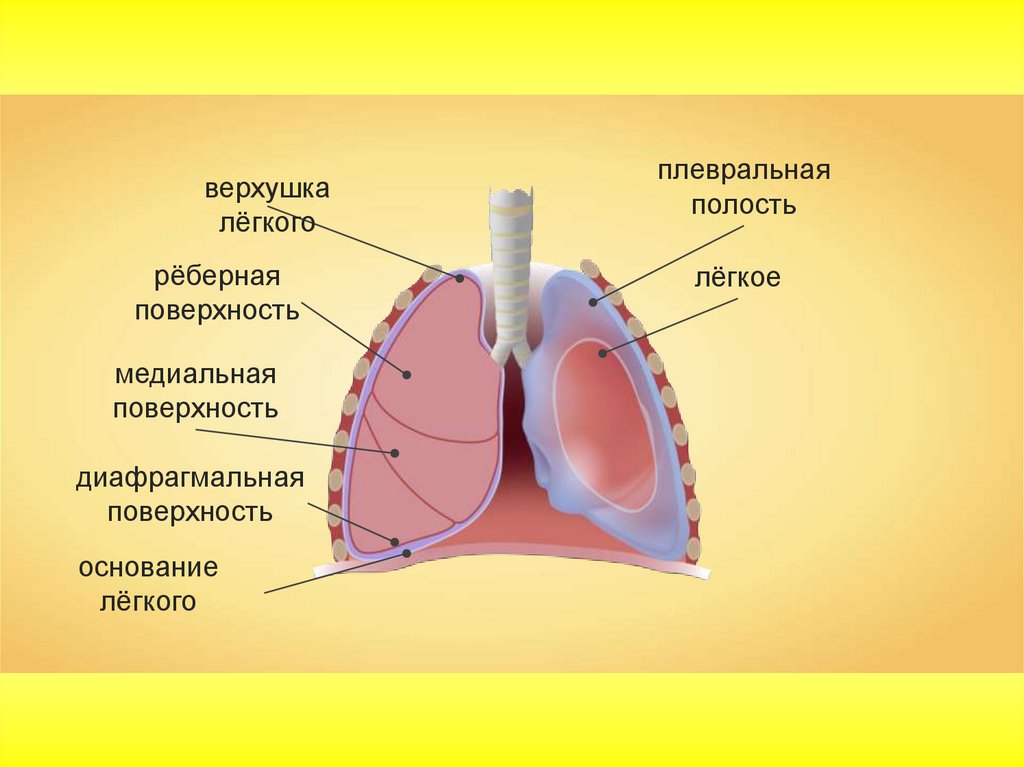

Роль легких в метаболических процессах